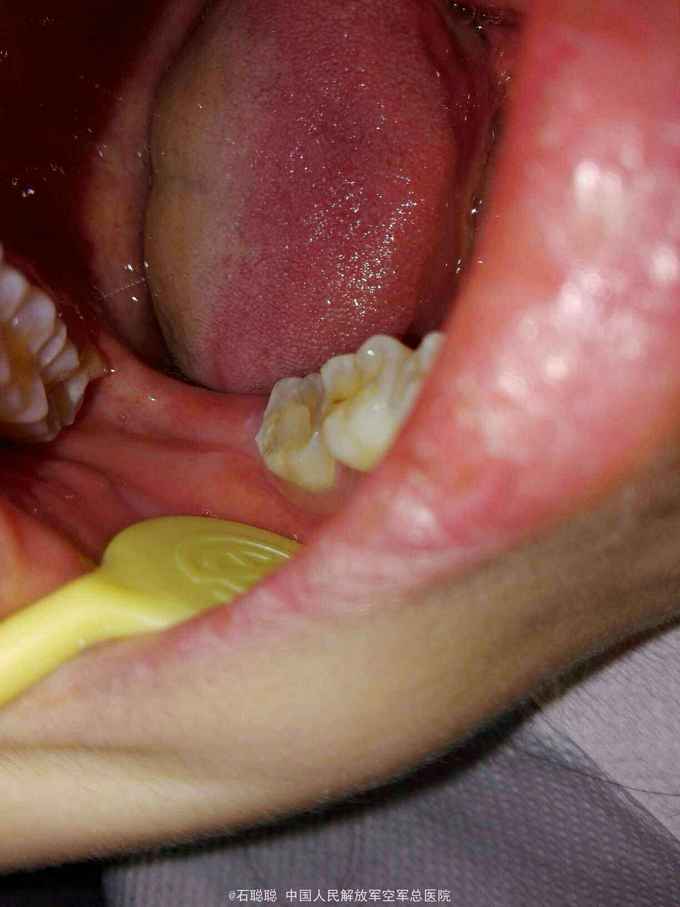

右下7全瓷嵌体冠修复

检查:47合面见白色暂封物完整在位,近中、远中、颊侧、舌侧壁厚度>2mm。咬合紧。叩痛-,无明显松动,牙龈未见明显异常,牙周探诊深度2mm。 根尖片:47根管内高密度充填影像,恰填,牙周膜、根尖区及根分叉未见异常

诊断:47牙体缺损 治疗计划:47全瓷嵌体冠修复 处置:47去除暂封,磷酸锌垫底,光固化覆合树脂充填,预备全瓷嵌体冠,取模,比色3M2,制作临时冠,调合,磨光,粘固 一周后复诊: 检查:临时冠完整在位,无松动,叩痛- 处置:去除47临时冠,试戴全瓷嵌体冠,调合,抛光,U200粘接 医嘱:勿用患牙咀嚼脆骨、坚果等过硬食物 口腔卫生宣教:巴斯刷牙法,牙线使用方法 不适复诊

讨论:这是常一例规的后牙根管治疗后要求修复的病历,患牙的对合略有伸长,咬合紧,尽管将对合做了降合处理,仍会降低龈合距离,削弱全冠的固位力,幸运的是47的四个轴壁均完整并且高度、厚度能满足制作嵌体冠的需要,可以利用髓腔制备固位形,明显改善了固位不足的状态。嵌体预备要点要满足轴壁无倒凹,有2-5度的合方外展,与牙冠就位道一致。